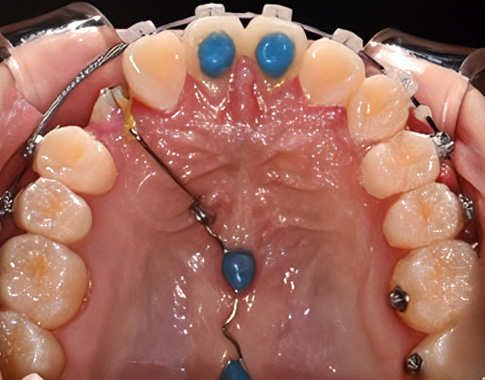

쓰러진 어금니 세우기

어린이 예방교정

공간 관리를 통해 건강한 치열 만들기

유치가 일찍 빠지거나 충치때문에 쓰러진 어금니를 바로 세우고, 영구치의 자연스러운 맹출을 유도합니다.